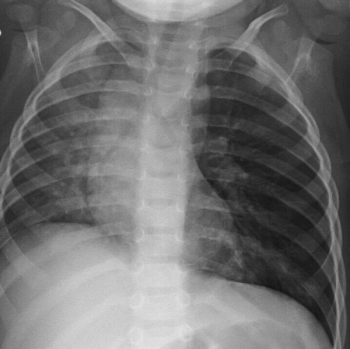

What is your diagnosis of a young child who presents with shortness of breath and distress?